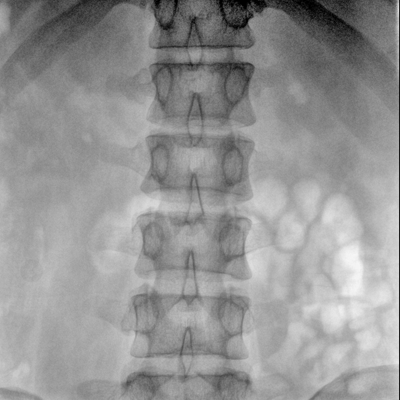

骨科: 經(jīng)皮錐體成形術(shù)、經(jīng)皮椎間盤臭氧治療術(shù)、胸脊椎固定、骨活檢、腰椎內(nèi)固定術(shù)等。

優(yōu)質(zhì)平板探測器、可靈活升降調(diào)節(jié)SID、獨特圖像處理系統(tǒng)、高品質(zhì)濾線柵,大視野成像清晰不失真。